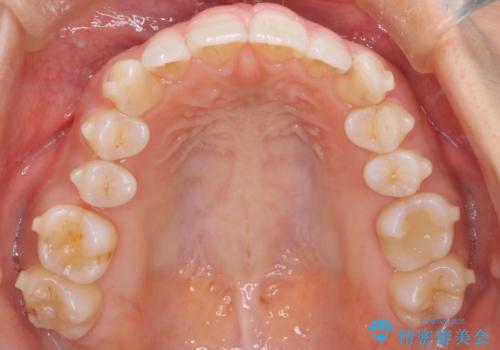

【インビザライン】前歯のねじれを治したい

- 前歯のガタガタを主訴に来院されました。

叢生の量は軽度でしたが臼歯の遠心移動を行い、インビザラインにて治療をしました。

叢生の改善に必要なスペースは遠心移動やIPRで作ることが可能です。今回は遠心移動をメインにスペースを作って叢生の改善を行いました。